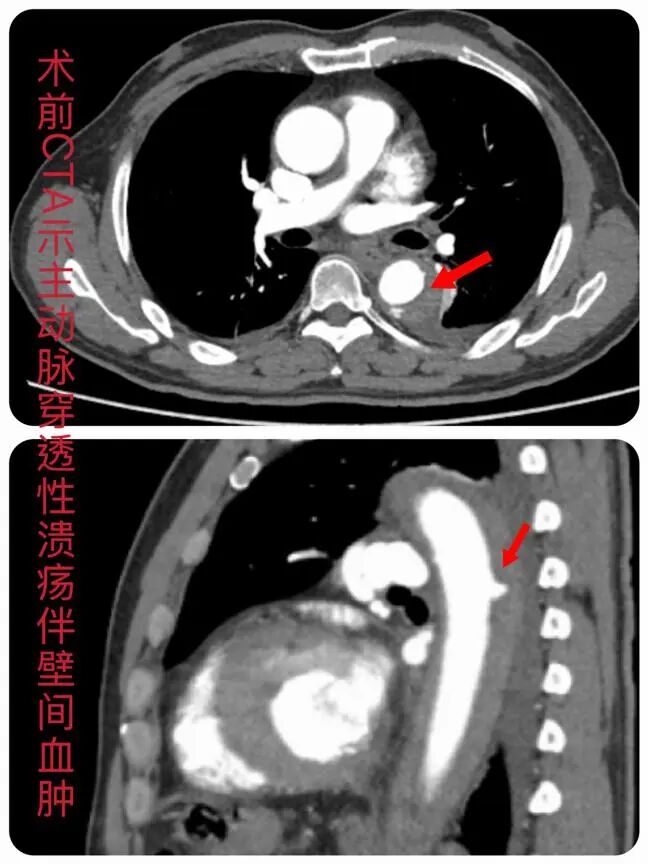

•主动脉CTA确诊:主动脉溃疡伴壁间血肿

这意味着,他的主动脉壁已经出现“溃烂”并形成血肿,病情进展极快,随时可能进展为主动脉夹层甚至破裂——主动脉夹层被称为“血管领域的猝死之王”,发病后48小时内死亡率高达50%,一旦破裂几乎无抢救可能,堪称“体内定时炸弹”。朴雄团队快速判断患者病情危重,随即收治入院积极救治。